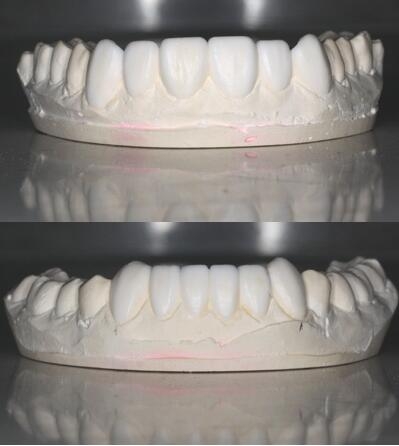

氟斑牙|瓷贴面修复——诊断蜡型制作

氟斑牙|瓷贴面修复——贴面制作